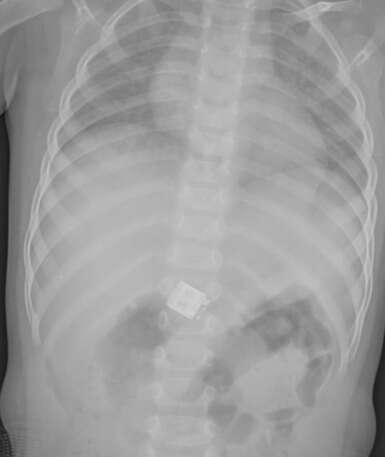

רופאי 'טרם' בעיר העבירו את התינוק לצילום רנטגן בו נצפה בגופו עצם זר. מתברר כי התינוק בלע MINI USB, צ'יפ המקשר עכבר wireless (אלחוטי) למחשב.

צילום הרנטגן חשף את הגוף הזר // צילום: 'טרם'

רופאי 'טרם' המליצו על המשך מעקב בתקווה שהגוף הזר ייפלט בצורה טבעית. ד"ר פרוג'י ממיון 'טרם' ציין כי "הסכנה הייתה שהגוף הזר ייכנס לנתיב אוויר או שיתקע בוושט, אבל בנס הדבר לא קרה ולכן בשלב זה מומלץ על מעקב".